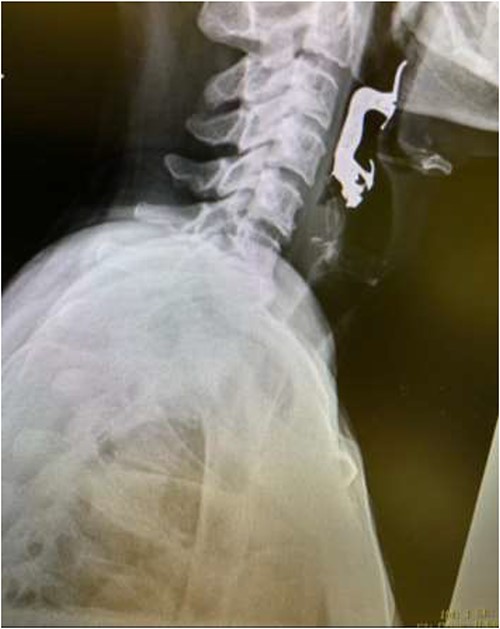

The first case is of a 7-year-old child presenting with a history of barbed wire inhalation. X-ray imaging of his neck and chest showed a radio-opaque object visible in the upper airway with sharp edges (Figs 1 and 2). Due to the position of the foreign body, endotracheal intubation was not feasible. A trial of apnoeic oxygenation using high-flow nasal oxygenation was used as an alternative, and this allowed for an unobstructed view of the larynx, facilitating the safe removal of the foreign body (Fig. 3).

Lateral neck X-ray showing a radio-opaque object with sharp edges visible.